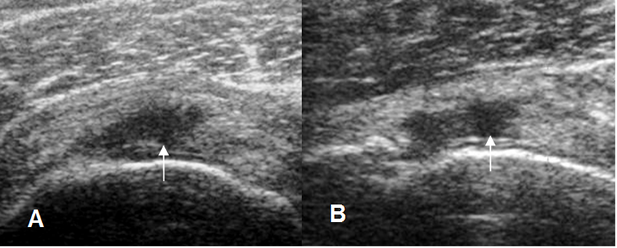

Fig 102. Ruptura parcial del supraespinoso.

A y B: Ecografía coronal. Zonas hipoecoicas en la superficie humeral, por ruptura parcial.